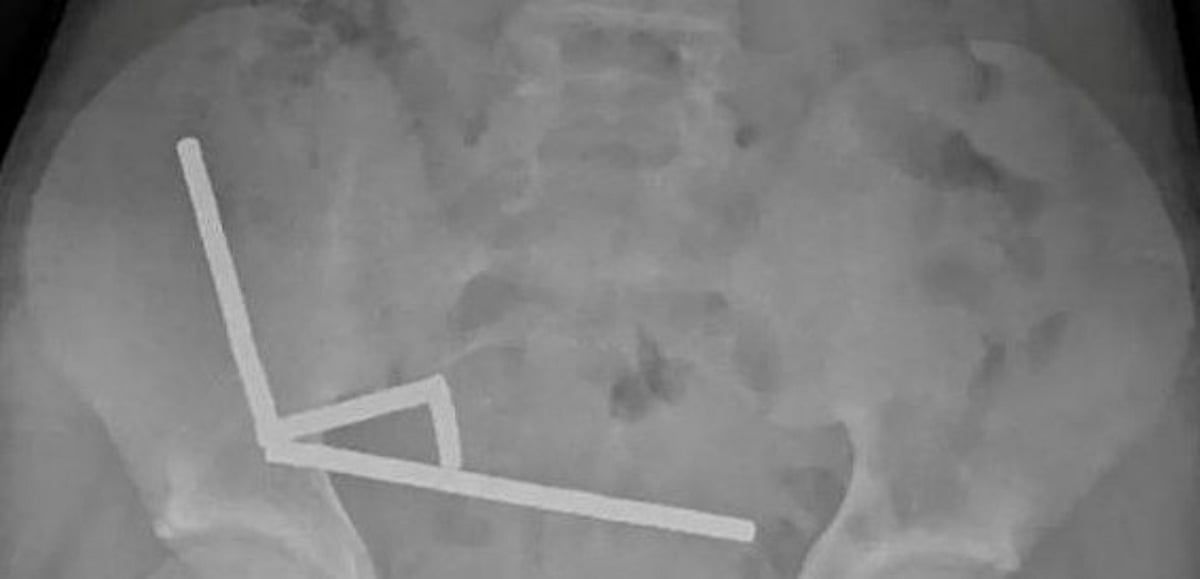

ورغم حظر هذه المغانط في منذ يناير 2013، أفاد الأطباء بأنها تم شراؤها من منصة التسوق "تيمو". وأظهرت الأشعة السينية تجمع المغانط في أربع خطوط مستقيمة داخل الأمعاء، حيث ظهرت في أجزاء منفصلة التصقت ببعضها بسبب القوى المغناطيسية، ما تسبب بضغط أدى إلى نخر في أربع مناطق من الأمعاء الدقيقة والأعور.